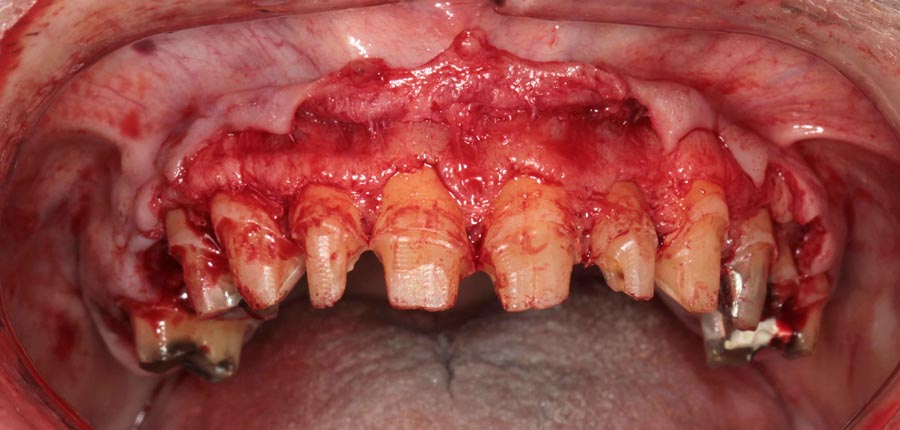

This is known as hard (bone) and soft tissue (gums) crown lengthening. To have loner teeth, many patients need their bone recontoured so that the gums do not grow back down to their original position.

All upper teeth extracted, implants and bone filler placed. Not, we did not remove any bone and attempted to disturb the gums minimally.